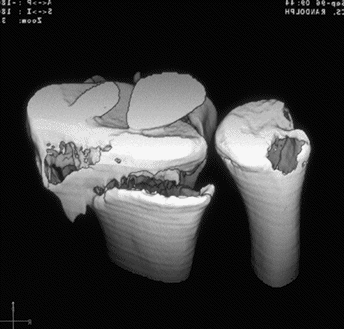

Case 3 CT